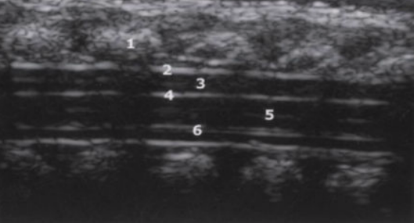

1

spinous processes

2

subarachnoid/dural layer

3

subarachnoid space filled with CSF

4

posterior margin of spinal cord

5

spinal cord with central echo complex

6

anterior margin of the spinal cord